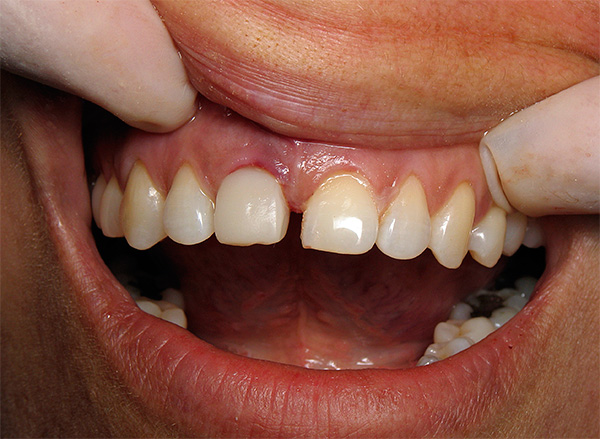

A foto abaixo mostra um exemplo correspondente (a inflamação começou 10 anos após a instalação do implante):

Abaixo, veremos o que pode ser feito para evitar esse resultado adverso.No entanto, antes disso, vamos falar sobre quais sensações são consideradas normais após o implante dentário e quais devem ser consideradas sintomas de peri-implantite, ameaçando evoluir para rejeição do implante.